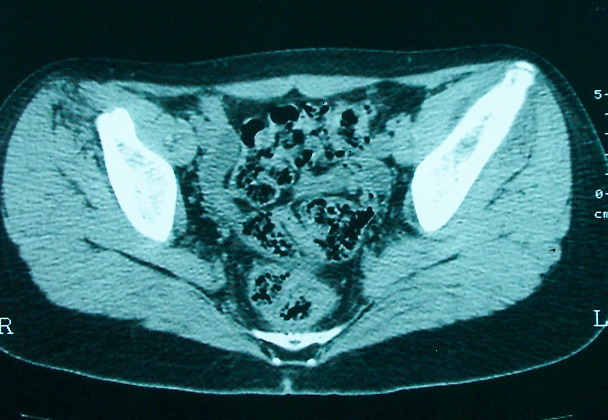

女 13岁 4月前有臀部肌肉注射史 3月前发热 最高体温38.5 2月前出现左髂骨疼痛 不剧烈能忍受 发热时高时低 按感冒治疗无好转 近日左髂骨疼痛加重 一星期前wbc 12.2 今日wbc9.5

左侧髂骨溶骨性骨质破坏,骨皮质侵蚀,灶周可见软组织肿块,支持考虑骨肉瘤可能性大。

髓腔起源,弥漫性溶骨性骨质破坏并软组织肿块,膨胀不明显,无显著钙化及瘤骨,有骨膜反应,结合年龄考虑恶性,尤文氏肉瘤可能性大。

左侧髂骨溶骨性骨质破坏,骨皮质侵蚀,灶周可见骨膜反应及软组织肿块,支持考虑骨肉瘤可能性大。